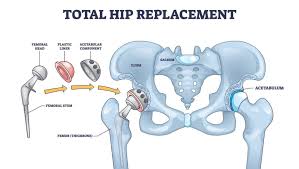

Varunam Super Speciality Hospital in Mandla offers a comprehensive hip replacement package under the Ayushman Bharat scheme, ensuring eligible patients receive advanced orthopedic care without financial burden. The hospital combines experienced orthopedic surgeons, modern surgical techniques, and patient-focused care to deliver safe and effective hip replacement procedures.

Equipped with advanced operation theatres, digital imaging systems, and specialized rehabilitation facilities, Varunam ensures accurate implant placement and improved joint function. The Ayushman Bharat hip replacement package covers hospitalization, surgery, implants, and essential post-operative care. With structured pre-operative assessment and physiotherapy support, Varunam is a trusted choice for hip replacement package Ayushman Bharat in Mandla.